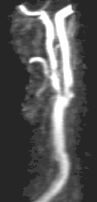

CE-MRA of the aortic arch and great vessels (left) into the brain, renal arteries (top), selective carotid bifurcation (top right) showing ICA/ECA stenosis, and 3-section run-off (very right) showing multiple stenoses, including long-segment bilateral SFA stenoses.